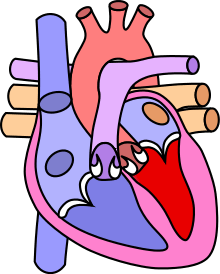

| Diagram of a healthy heart and one with tetralogy of Fallot | |

The cause is typically not known. Risk factors include a mother who uses alcohol, has diabetes, is over the age of 40, or gets rubella during pregnancy. It may also be associated with Down syndrome.[4] Classically there are four defects:[2]

- a ventricular septal defect, a hole between the two ventricles

- pulmonary stenosis, narrowing of the exit from the right ventricle

- right ventricular hypertrophy, enlargement of the right ventricle

- an overriding aorta, which allows blood from both ventricles to enter the aorta

As such, by definition, tetralogy of Fallot involves four heart malformations which present together: